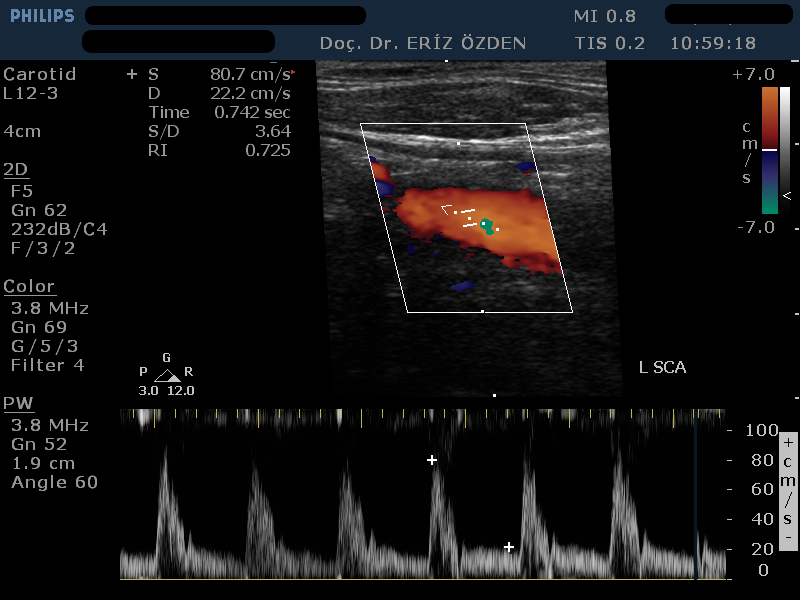

Renkli Doppler Ne Demek, Nasıl Yapılır? Ultrasonografi cihazı Renkli Doppler özelliğine sahipse, damarların içindeki kan akımını renkli olarak görmek mümkündür. Renkli Doppler Ultrason adı verilen bu yöntem sayesinde damarlardaki daralma ve tıkanıklar saptanır. Kan akım hızına yönelik ölçümler yapılır. Kanın damaraı tam olarak doldurup doldurmadığı, kan akımının yönü ve saniyedeki akım miktarı öğrenilir. Özellikle boyun damarlarındaki daralmalarda Karotis Renkli Doppler çok sık kullanılır.

Vertebral Doppler Nedir? Şah damaraı denilen Karotis Arterleri dışında, beyne giden diğer atar damarlara vertebral arter adı verilir. Vertebral arterler beybin arka kısımlarının ve beyinciğin kanlanmasından sorumludur. Bazı hastalarda tukanıklık ya d darlık gelişir ve bu da özellikle baş dönmesi, kulak çınlaması gibi şikayetelre neden olur. Baş dönmesi, dengesizlik şikayetleri olan hastalarda, karotis dopplere ek olarak mutlaka verrebral arter doppler tetkiki de yapılmalıdır.